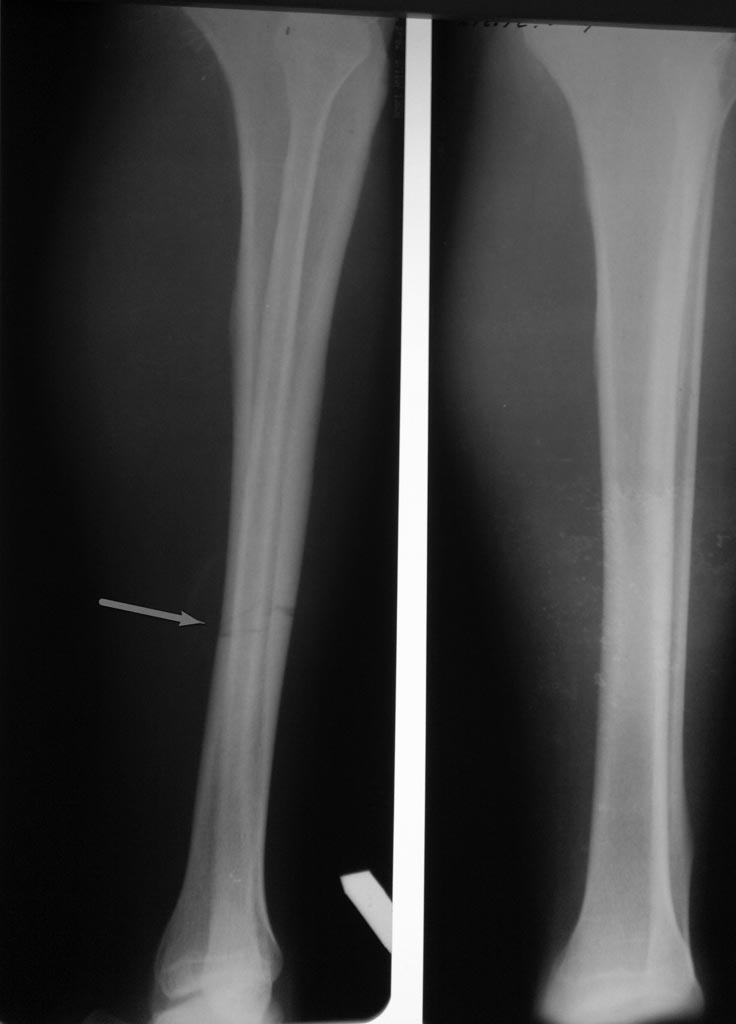

[Ortho] Незавершенный перелом

лет 38